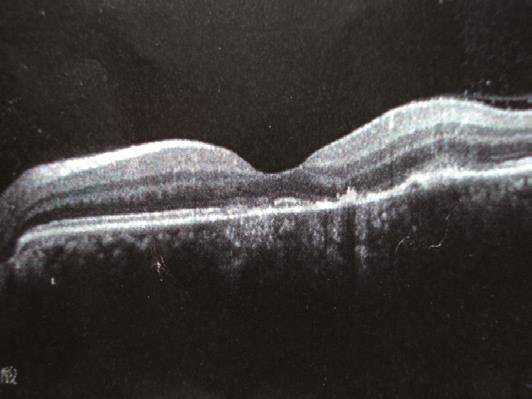

入院前5个月,无明显原因出现左眼胀及眼前闪光,伴视力下降和视野缺损,于当地医院眼底及FFA(图1a~b)检查见(2009年9月)黄斑区偏下可见多处边界清及边界不清的高荧光区(随显影时间延长而增强),诊断为局灶性脉络膜炎,予以泼尼松治疗,症状缓解。之后激素逐渐减量至停用。此后类似症状反复发作3次,均为激素治疗有效、停药后复发。10天症状再次发作,视野缺失明显,于2010年2月来我院眼科就诊,OCT示RPE层局部凹凸不平(图2),诊断同前,疑风湿病,于2010年2月22日收入我科。

图2

OCT显示RPE层局部凹凸不平